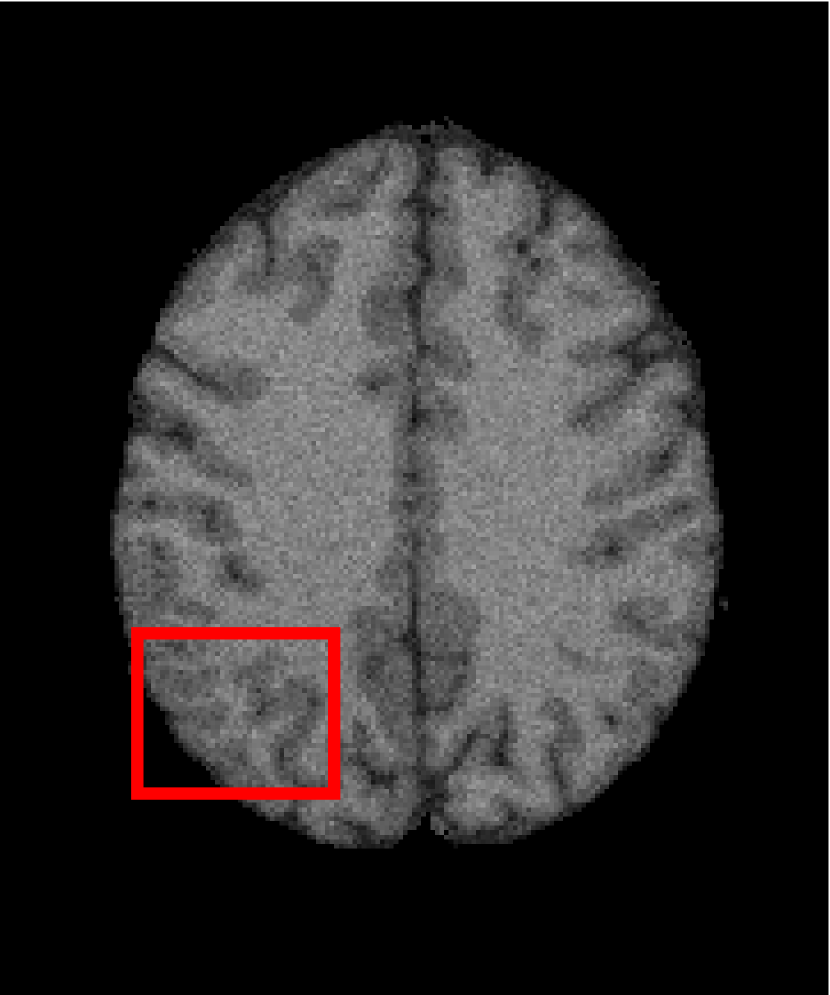

Next, we representatively segment five medical images from BrianWeb. They are represented as five slices in the axial plane with a sequence of 70, 80, 90, 100 and 110, which are generated by T1 modality with slice thickness of 1mm resolution, 9% noise and 20% intensity non-uniformity. Here, we set c=4𝑐4c=4 for all cases. The comparison between WRFCM and its peers are shown in Fig. 9 and Table II. The best values are in bold.

Figure 9: Segmentation results on five medical images. The parameter: ϕ=5.35italic-ϕ5.35\phi=5.35. From top to bottom: noisy images, ground truth, and results of FCM_S1, FCM_S2, FLICM, KWFLICM, FRFCM, WFCM, DSFCM_N, and WRFCM.

By a view of the marked red square in Fig. 9, we find that FCM_S1, FCM_S2, FLICM, KWFLICM and DSFCM_N are vulnerable to noise and intensity non-uniformity. They give rise to the change of topological shapes to some extent. Unlike them, FRFCM and WFCM achieve sufficient noise removal. However, they produce overly smooth contours. Compared with its seven peers, WRFCM can not only suppress noise adequately but also acquire accurate contours. Moreover, it yields the visual result closer to ground truth than its peers. As Table II shows, WRFCM obtains optimal SA, SDS and MCC results for all five medical images. As a conclusion, it outperforms its peers visually and quantitatively.